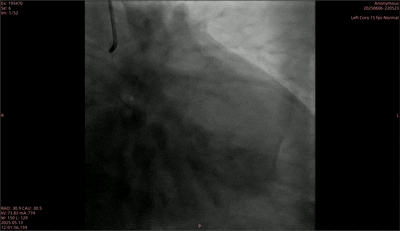

Preoperative angiography showed diffuse long lesions in the middle segment of the anterior descending artery, with stenosis up to 80% and TIMI grade 3 blood flow; The stenosis in the distal segment of the circumflex branch is the heaviest at 80%, with TIMI grade 3 blood flow; The original stent in the middle section of the right coronary artery has unobstructed blood flow, mild intimal hyperplasia inside the stent, and TIMI grade 3 blood flow. After evaluation, the treatment team has decided to first treat the anterior descending artery disease and ensure good treatment before using the Zhengzheng Medical Coronary Reshaping Catheter to treat the patient's distal circumflex branch.

Preoperative

During the surgery, two drug-eluting stents were first implanted in the anterior descending artery, and repeated imaging showed the narrowing was relieved. Subsequently, a pre expanded balloon with a size of 2.0mm × 15mm was used to pre expand the distal segment of the circumflex branch. After expansion, the diameter stenosis was 25%, and the blood flow was TIMI grade 3. However, a B-type dissection appeared at the lesion site after pre expansion. Subsequently, a 2.0mm × 30mm rectangular medical coronary artery remodeling catheter was used to dilate the blood vessels with a pressure of 6atm, and laser treatment was initiated simultaneously. In the end, the postoperative imaging results showed good dilation effect at the stenosis site, residual stenosis of 20%, disappearance of the original dissection, TIMI grade 3 blood flow, and successful completion of the surgery.

Postoperative